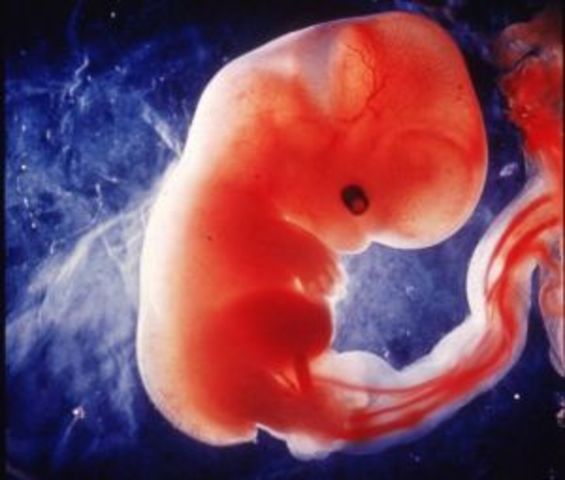

• SEMANA 10

SEMANA 10

Mide entre 28 y 29 mm y pesa casi 5 gramos, comienza la formación de codos y rodillas. Esta semana es la última que se le llamará embrión, después pasará a ser feto. Ya se encuentra totalmente formado, ahora solo falta la maduración.

• SEMANA 9

SEMANA 9

Los miembros son más largos, los dedos comienzan a separarse. El sexo ya está determinado